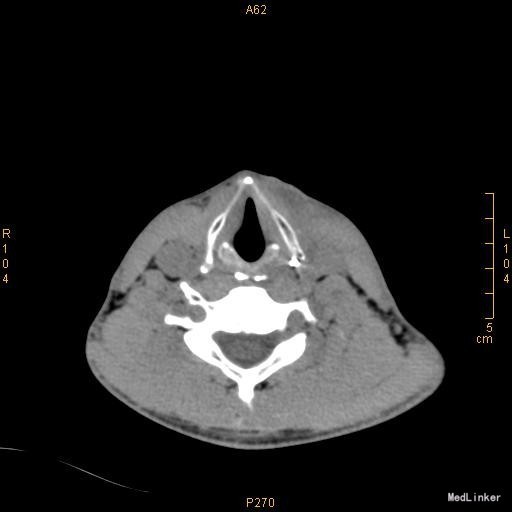

查体:颈前有明显手术瘢痕,左侧颈外侧区可触及一约3cm×3cm大小肿物,质韧,边界不清,表面光滑,不可随吞咽上下移动,触痛明显,颈部未闻及明显血管杂音。 辅查:2015-11-16我院颈部增强CT示左侧颈部感染,多发脓肿形成。

该患者在诊断上是有些困难,颈部多发脓肿是明确的,但是瘘口的位置不好确定,从而未能确诊,8年前患者行上消化道钡餐检查,诊断“食管瘘”,但是我们从8年前的影像上看,瘘口的位置太高,不像是食管的瘘口,考虑是不是梨状窝的瘘道,为了进一步确诊,我们给患者行了胃镜检查,结果胃镜发现左侧梨状窝有1个3mm大小的小孔,胃镜未能通过,食管未见明显的瘘口。为了更加明确瘘口的位置,我们与影像科商议后决定口服造影剂后行颈部CT平扫,因怕钡餐沉积在脓肿内不好排出,我们采用了口服碘化油。此次影像明确了瘘口的确在左侧梨状窝。最终诊断:左侧颈部多发脓肿;左侧梨状窝瘘道形成。 治疗:入院后予抗感染、禁食、营养支持等治疗,患者感染得以控制,请耳鼻咽喉科会诊后建议转科治疗。